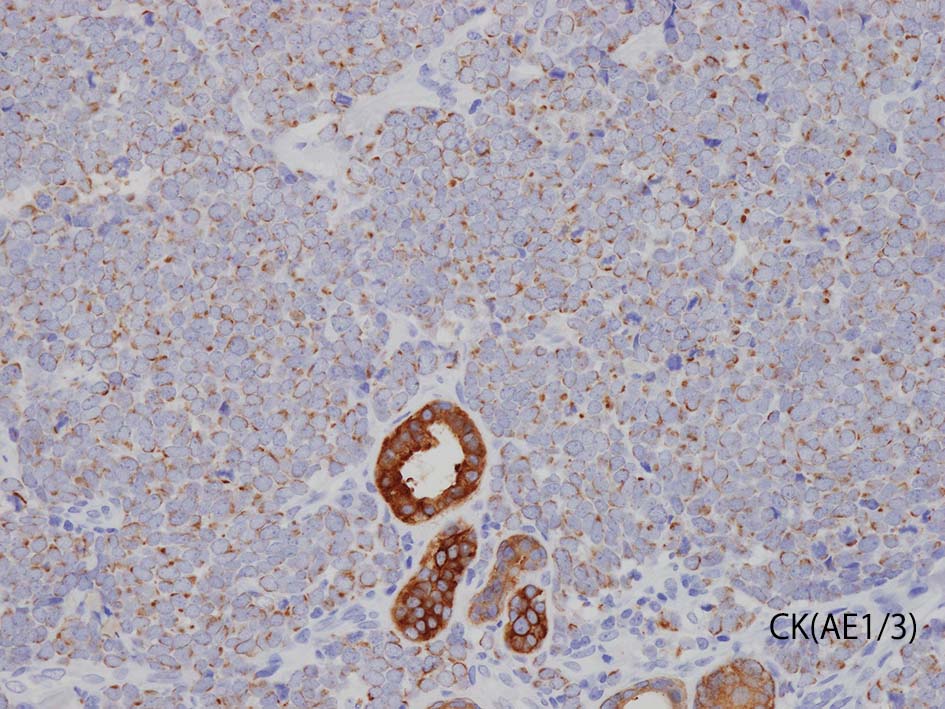

- 陽性上皮系マーカ; CAM5.2, AE1/3, CK20, BerEP4, EMA

TTF-1;肺小細胞癌の83-100%で陽性. Merkel cell carcinomaでは通常陰性であり, CK20のパターンとあわせて鑑別に有用である.

CK(AE1/3); CK20は含まない, のほうがdot-likeな染まりをしている. CK20は膜にも陽性になっている. LCAは陰性. 神経内分泌マーカのchromograninA, synaptophysinは陽性.